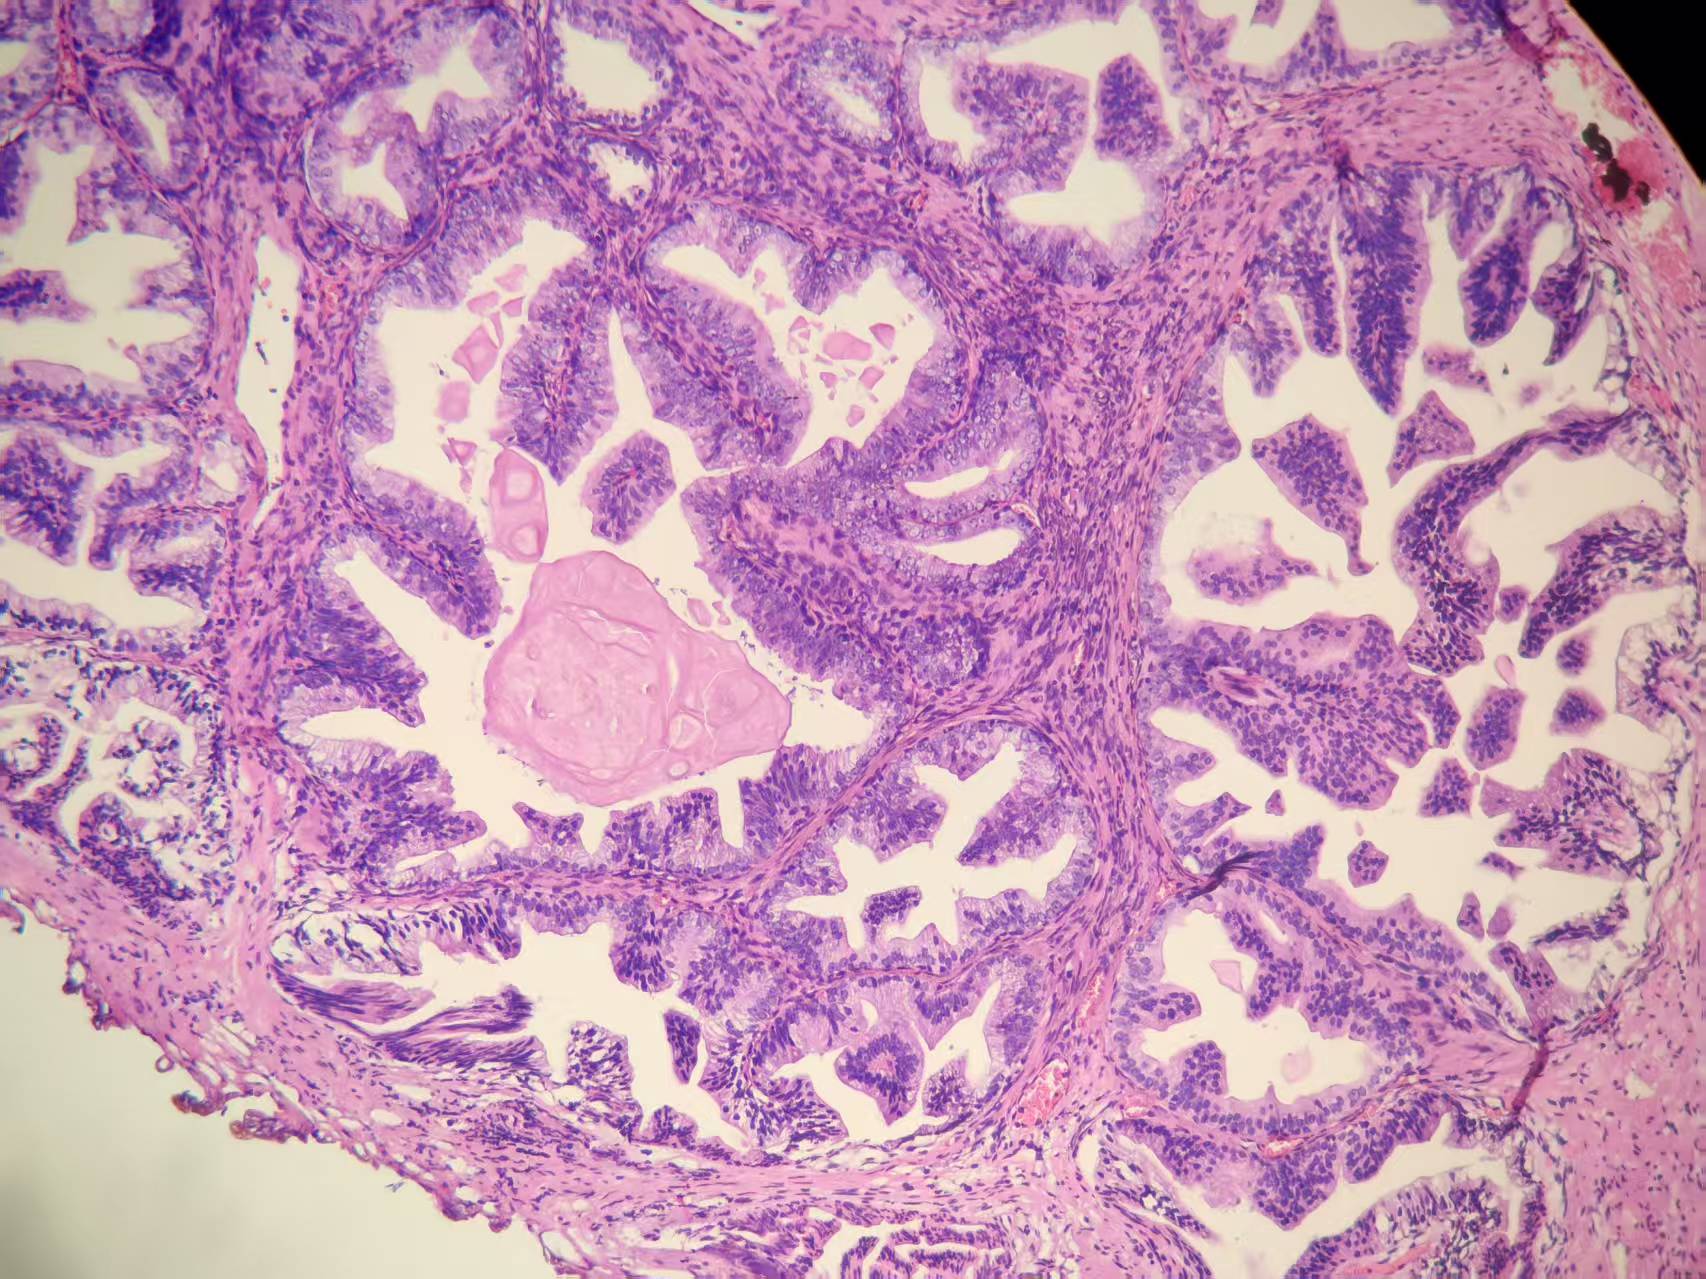

前列腺PIN?

发现肉眼血尿5月余,PAS 5.7

经尿道前列腺等离子电切组织

本例核仁巨大,值得关注!

嗜酸性大核仁,胞浆透亮,PIN没问题。还是组化一下吧,